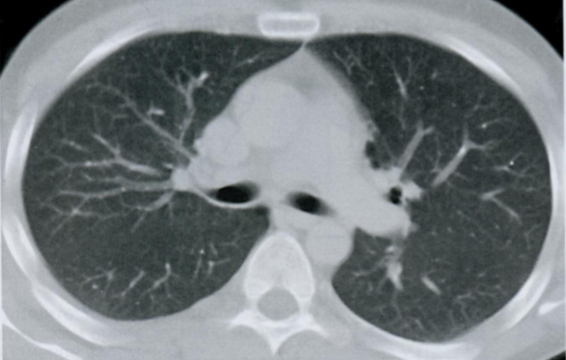

КТ грудной клетки №5

Назовите все анатомические структуры, которые Вы знаете, на данном КТ срезе (10).

Найдите грудные позвонки и грудину. Затем правое предсердие, восходящую и нисходящую аорту, легочный ствол, левое предсердие и легочные сосуды, непарную вену и пищевод.

A

26 - грудные позвонки

24 - грудина

2 - правое предсердие

7 - восходящая аорта

9 - легочный ствол

3 - левое предсердие

10 - сосуды легких

8 - нисходящая аорта

15 - непарная вена

16 - пищевод

Синим цветом отмечены номера сегментов.